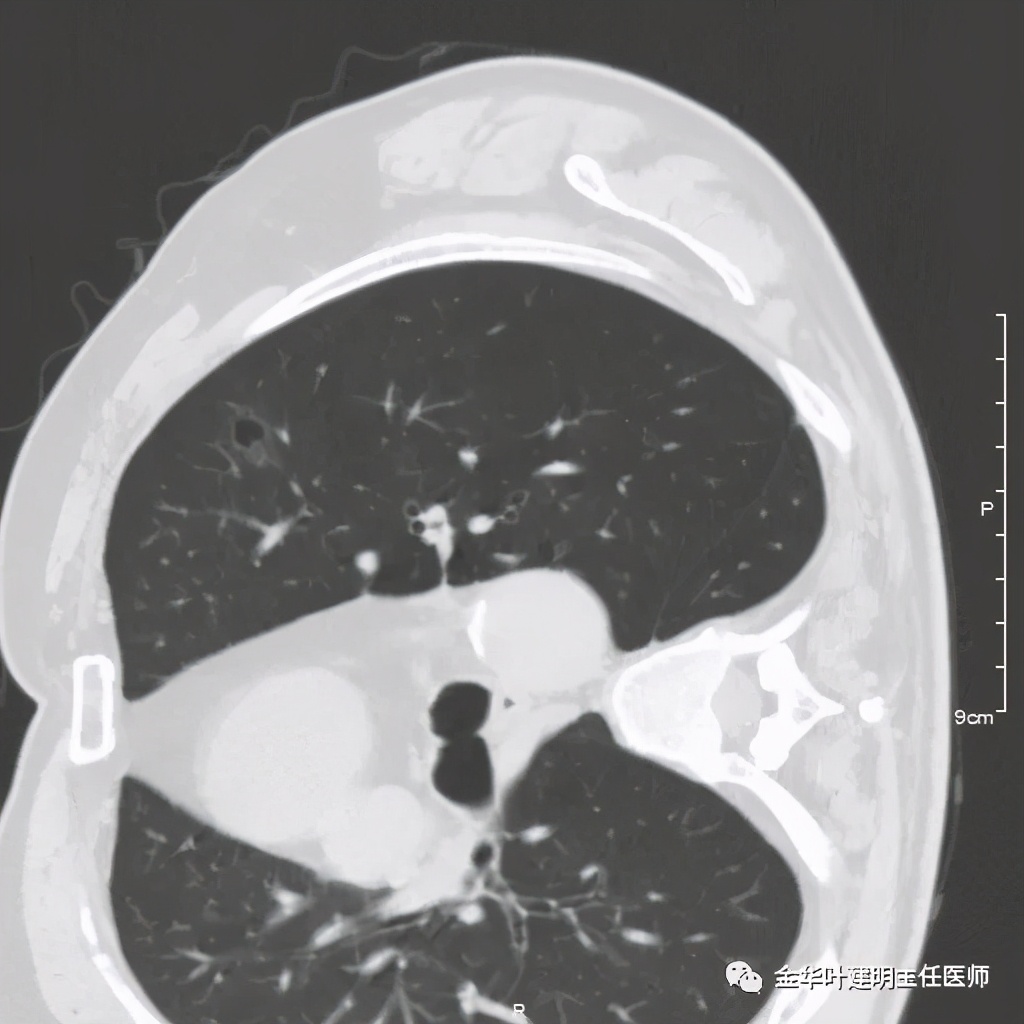

七、浸润性腺癌的其他型:

上图病例为实性,病理上实体型占80%,腺泡型占20%

上图此例也是实性结节,病理报告:实体型伴神经内分泌;

上图此例的实性肿块,病理是:微乳头为主,部分实体型,当时没注明占比;

上图此例实性结节,是实体型,我们发现其影像特征: 病灶有浅分叶、细毛刺、支气管截断征、膨胀性,密度高而密 (比腺泡型实、比粘液癌高、比鳞癌或小细胞癌更具膨胀性)。

但是上面这几例,因为不管怎样的组合,都是实性密度+实性密度,这时仅从影像上就非常难以判断具体的亚型,不过,我们要根据相关的影像特征判断它为恶性,而且该尽早取得病理依据,能手术的要抓紧、不能手术的也要穿刺等得到病理类型的确诊后积极治疗,这就够了!